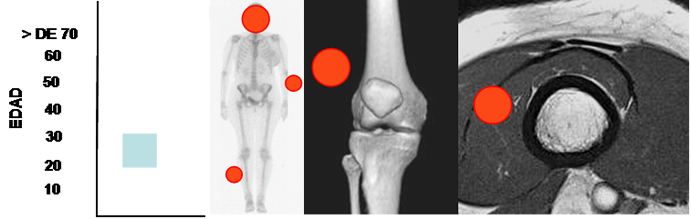

Fig 179 A. Neurofibroma.

Mayor frecuencia entre los 20 y 30 años. Lesión de tejidos blandos con predominio en la cara, el cuello, complejo VII-VIII par craneal y extremidades.